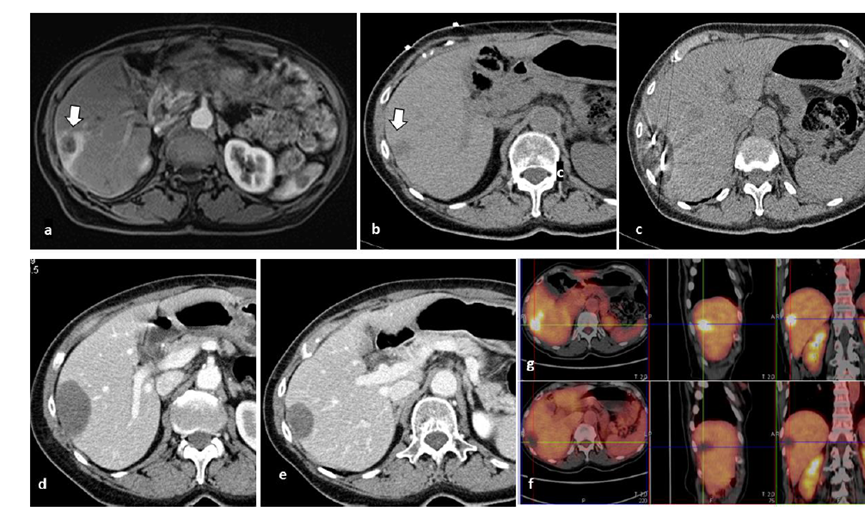

undefined

62岁女性,肝转移(卵巢癌)肿瘤的完全消融病例

(a)轴向CT显示病变位置毗邻心脏和上腔静脉(黑色箭头)。

(b)术中轴向CT扫描:使用三个冷冻探针。

(c)冠状面和(d)矢状面显示冰球毗邻心包。

1个月后的轴向(e)和冠状位(f)增强CT扫描显示低密度区域,由于肉芽组织反应引起的边缘增强。